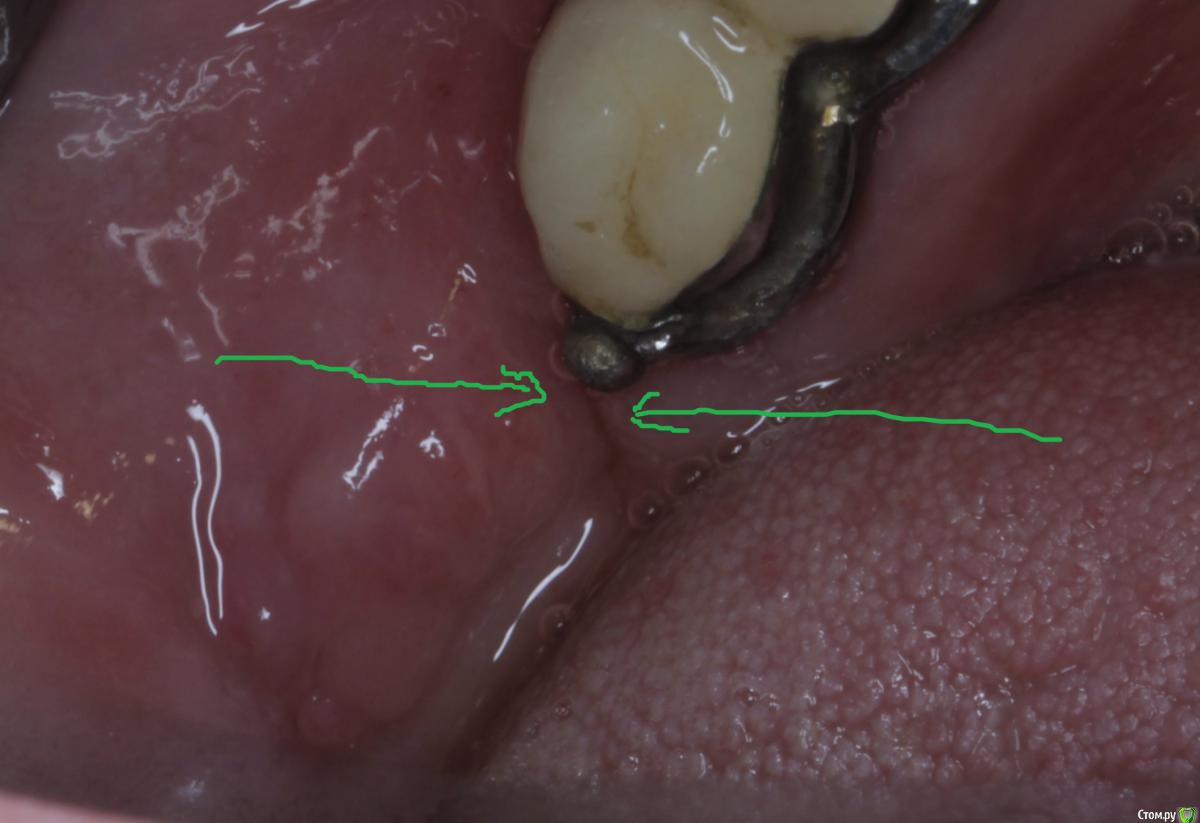

Acidrocker Опубликовано 18 апреля, 2015 Автор Поделиться Опубликовано 18 апреля, 2015 Прошло три недели, боль после операции полностью не прошла, вчера была на осмотре, болезненности при пальпации не было нигде, только обнаружил свищ, сегодня при осмотре болезненность, небольшое серозно-гнойное отделяемое (до 0.5 мл). Пока промываю хлоргексидином и назначил дома полоскать 0,2%-ным раствором. Что это может быть? Как поступить? Свищ на фото обозначил. Ссылка на комментарий